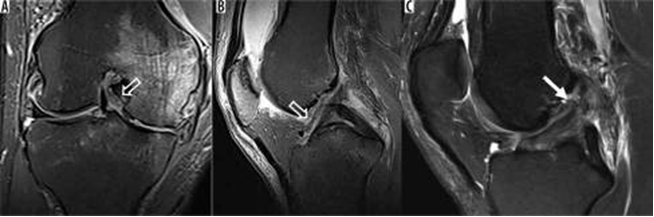

Hình 9. Rách sụn chêm và mô hạt đang lành sau mổ. A là hình ảnh T1 xóa mỡ sau khi tiêm thuốc tương phản trong khớp với tín hiệu tuyến tính sụn chêm bên có giá trị trung gian về cường độ tín hiệu (mũi tên trắng), so với chất tương phản sáng được tiêm vào không gian khớp (mũi tên mở), có thể đại diện cho mô hạt trong sụn chêm bên đã được phẫu thuật sửa chữa trước đó. B là hình ảnh T1 xóa mỡ sau khi tiêm thuốc tương phản nội khớp cho thấy khiếm khuyết cường độ sáng tương phản (mũi tên đen) ở sụn chêm giữa, biểu thị vết rách xuyên tâm.

Hình 14. Dây chằng chéo sau: rách một phần và thoái hóa niêm mạc. A là hình ảnh pd xoá mỡ sagital với tín hiệu tăng lên ở phần giữa của dây chằng chéo sau thể hiện vết rách một phần trước đó (mũi tên). B là hình ảnh pd xoã mỡ cho thấy sự xuất hiện "đường ray xe điện" (mũi tên) của dây chằng chéo sau phù hợp với thoái hóa niêm mạc

Hình 15. Đứt dây chằng chéo sau. Hình ảnh pd xoá mỡ sagittal cho thấy dây chằng chéo sau bị đẩy hoàn toàn từ sự chèn ép của nó (mũi tên).